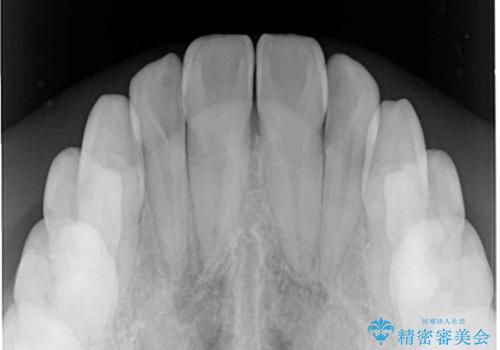

- 奥歯の反対咬合を気にして来院された患者様です。

反対咬合は上顎骨の幅が下顎骨よりも小さいことが原因なので、拡大装置により骨幅を広げて上下関係を改善し、その後インビザラインにて歯並びを整えることとしました。

反対咬合が改善され、食いしばり癖もなくなり、顎関節の負担が軽減されました。

上顎骨を拡大したことで前歯に隙間ができ、1ヶ月ほど恥ずかしい時期がありましたが、しっかりとした咬み合わせに仕上がり、患者様には大変満足していただきました。